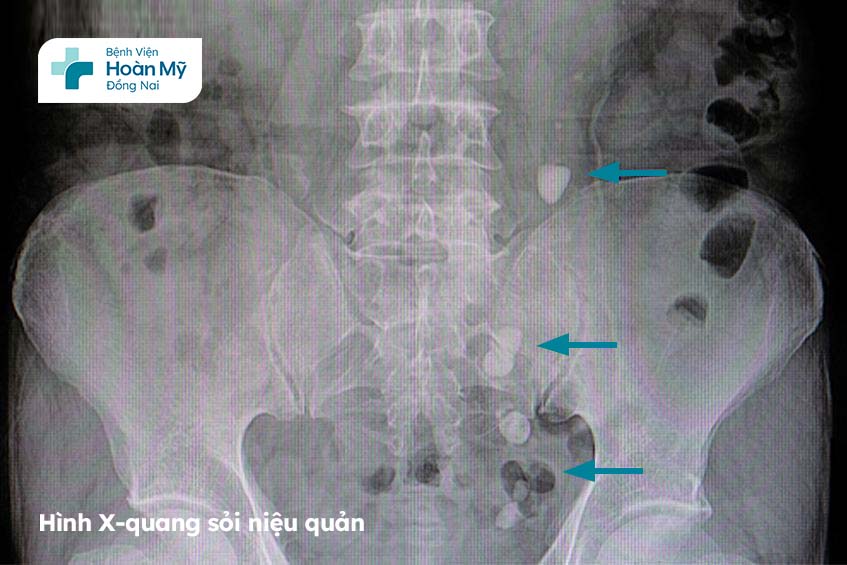

Hình ảnh X-quang của sỏi niệu quản Bệnh viện Hoàn Mỹ Đồng Nai